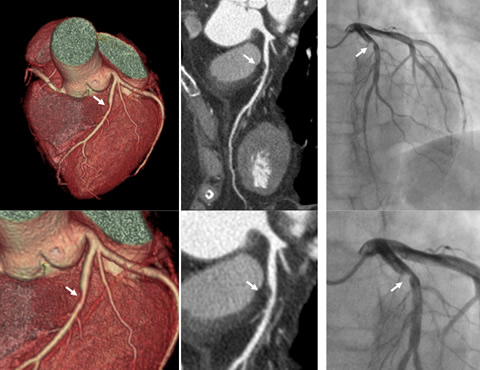

心臓CTは、冠動脈造影に匹敵する詳細な画像が得られ、プラークによる冠動脈の狭窄や閉塞の診断ができます。さらに、急性冠症候群の原因となる冠動脈の壁性状の評価も可能で治療方針の決定に役立っています。

- 冠動脈の石灰化が強い場合、心臓CTで狭窄の有無の判定は困難である(下図参照)。